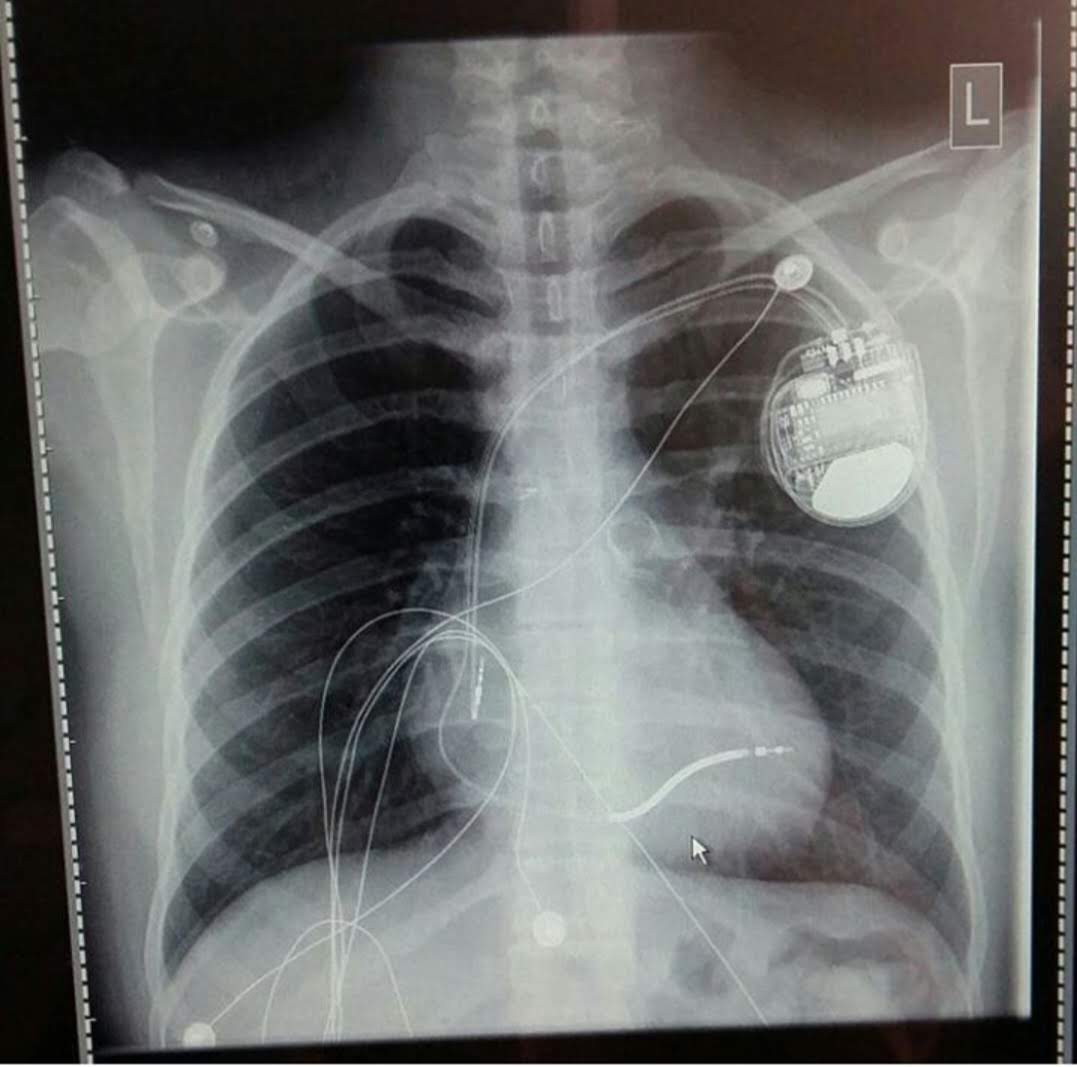

At Vital Hearts 💓 our mission is to raise awareness for heart health, inspire resilience through lived experience, and use creativity in modelling and cosplay to shine a light on the importance of caring for every heart. We’re dedicated to education, advocacy, and sharing stories that prove recovery and strength are possible.

🌏 WIN NEWS: World Heart Day Feature - Sharing My Story 📰 By Leanne Madigan VIDEO This World Heart Day was one I’ll never forget. I had the incredible opportunity to be featur…